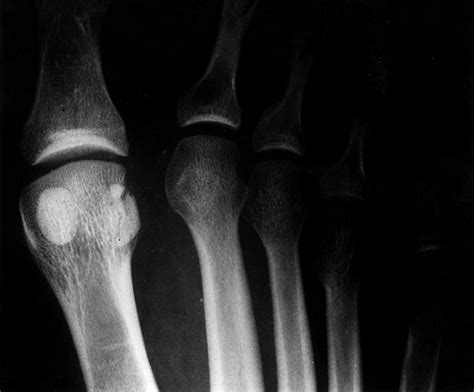

• X-Rays: X-ray images to visualize the bones and identify any fractures.

• MRI or CT Scan: Advanced imaging techniques to provide a more detailed view of the sesamoid bones and surrounding tissues.

• Bone Scan: A nuclear medicine test that can detect stress fractures that may not be visible on X-rays.